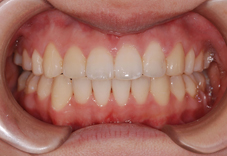

笑った時の八重歯を気にして来院された患者さまです。

写:矯正治療前、右:治療後

上下とも八重歯の状態が治療後は改善しています。歯並びがきれいに並んで、その後ホワイトニングも行いました。

前歯の歯並びのでこぼこも解消しました。

上の前歯が前に突出していた状態も改善して前歯が引っこんでいます。

前歯の歯並びが改善すると笑った時の雰囲気もかなり変わりますよね。この後すぐに結婚式が控えておりましたが、ホワイトニングも行って挙式に臨んでいただきました。